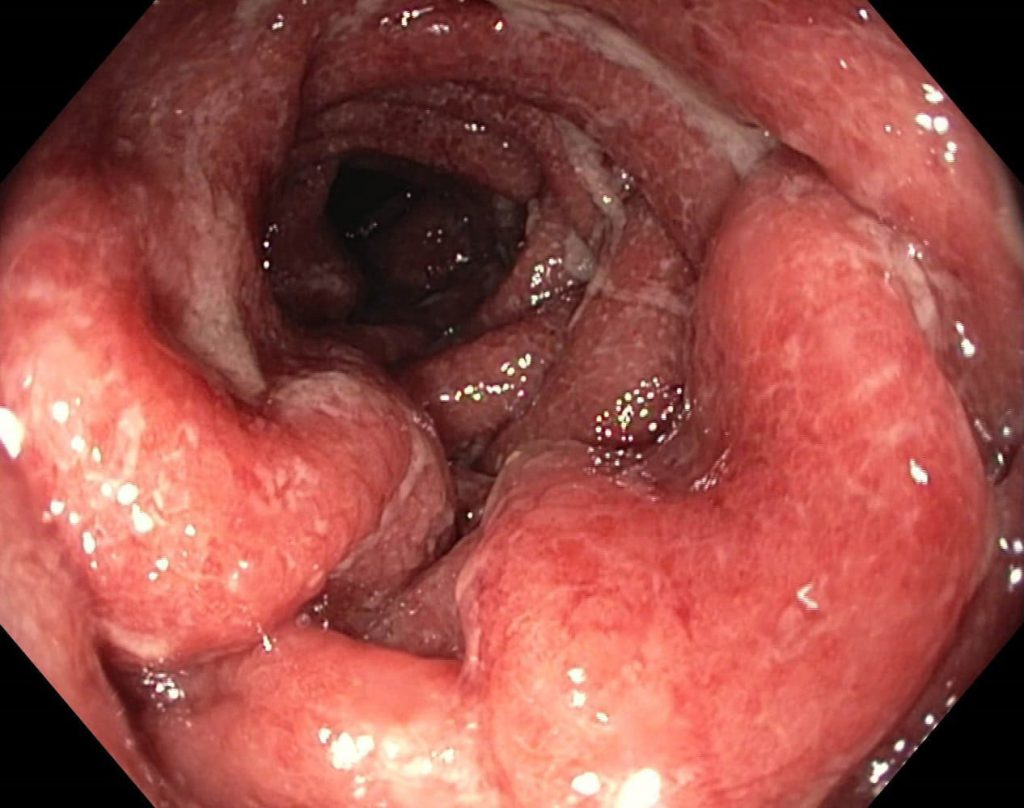

لنفوم مالت

لنفوم مرتبط با مخاط یا مالتوما، زیرگروهی از لنفومهای غیرهوچکین (NHL) ناشی از لنفوسیت B میباشد؛ که اغلب افراد مسن را در دهههای ۷-۸ زندگی درگیر میکند. مالتوما میتواند به دو نوع گاستریک و غیرگاستریک تقسیم شود. مالتومای گاستریک با عفونت هلیکوباکترپیلوری همراهی دارد، در حالی که مالتومای غیرگاستریک با بیماریهای خودایمن (مثلاً تیروئیدیت هاشیموتو و سندرم شوگرن) همراهی دارد.